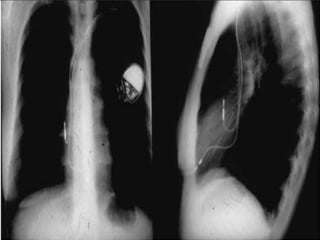

Desde 2010, já existem mercado brasileiro os

marca-passos MRI, que são compatíveis com

ressonância magnética.

• Esses marca-passos suportam campos eletromagnéticos intensos

e, por isso, permitem uma vida praticamente normal.

• Hoje em dia, a ressonância magnética é um exame que será

necessário para a maioria das pessoas: para doenças da idade

(coluna, AVC, quadril, doenças neuro-degenerativas), e também

para doenças dos jovens (lesões de joelho, ombro, quadril).

• É função médico cirurgião cardíaco que for fazer o implante do

marca-passo, solicitar ao convênio a prótese que traz essa nova

tecnologia.

Desde 2010, jáexistem mercado brasileiro os marca-passos MRI, que são compatíveis com ressonância magnética. TELEFONE RESSONÂNCIA MAGNÉTICA FORNO MICROONDAS

• Esses marca-passossuportam campos eletromagnéticos intensos e, por isso, permitem uma vida praticamente normal. • Hoje em dia, a ressonância magnética é um exame que será necessário para a maioria das pessoas: para doenças da idade (coluna, AVC, quadril, doenças neuro-degenerativas), e também para doenças dos jovens (lesões de joelho, ombro, quadril). • É função médico cirurgião cardíaco que for fazer o implante do marca-passo, solicitar ao convênio a prótese que traz essa nova tecnologia. INTERESSANTE !